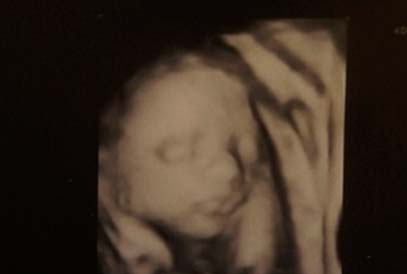

Voici à quoi ressemble le fœtus à 24 semaines:

À ce moment, l'échographie est rarement prescrite. Mais si vous allez à cette étude, vous pouvez certainement voir le visage de votre enfant. Ses caractéristiques ne changeront pas jusqu'à la naissance même.

Photo échographie: